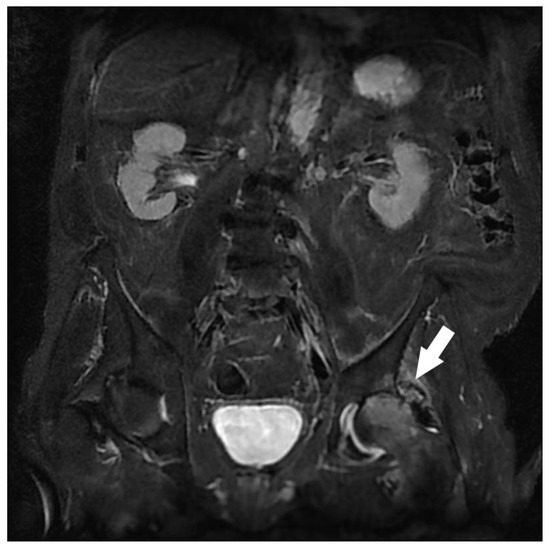

| Gluteal Muscles | Gluteal tendinobursitis | 21 |

| Others | Endometrioma with posterior deep pelvic endometriosis | 1 |

| Ischio-femoral impingement | 1 | |

| Retroperitoneal mass syndrome with urinary obstruction | 1 |